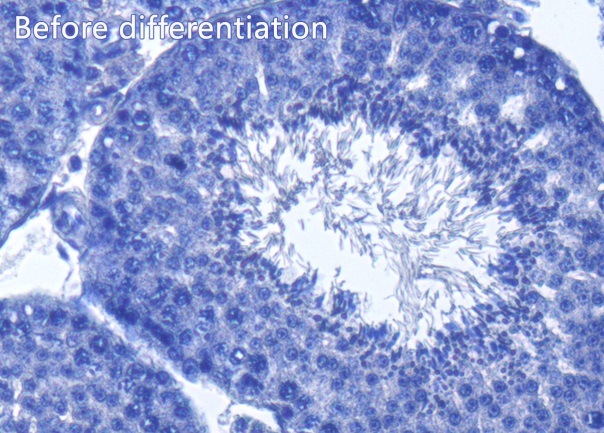

本盐酸乙醇分化液的组分经过反复优化,分化速度非常快,通常仅需分化2-5秒左右,可以非常快速地完成分化,特别适合对于苏木素染色分化操作非常熟练的实验人员。苏木素染色后的组织切片经本分化液分化处理后,核质着色更加清晰分明。本产品用于石蜡切片苏木素染色后的分化前后同一视野效果图参考图1。

图1. 本产品用于小鼠睾丸石蜡切片苏木素染色后同一视野分化前后的实拍效果图。左图为未经分化处理的效果图,右图为经本产品分化处理后的效果图。从图中可见,经本产品分化处理后,苏木素染色的细胞核呈现蓝色,核质清晰分明,背景呈现纯净的白色。本图仅作参考,不同的样品不同的检测条件,实际获得的结果可能有所差别。Scale bar, 100μm。